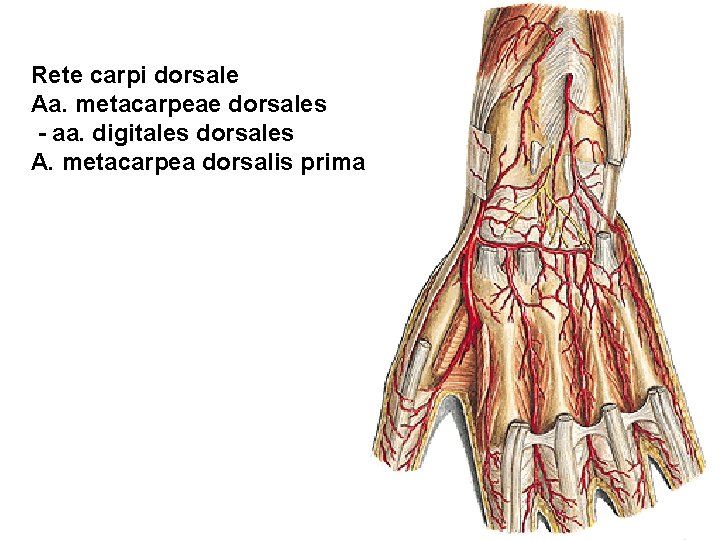

Rete carpi dorsale Aa. metacarpeae dorsales - aa. digitales dorsales A. metacarpea dorsalis prima